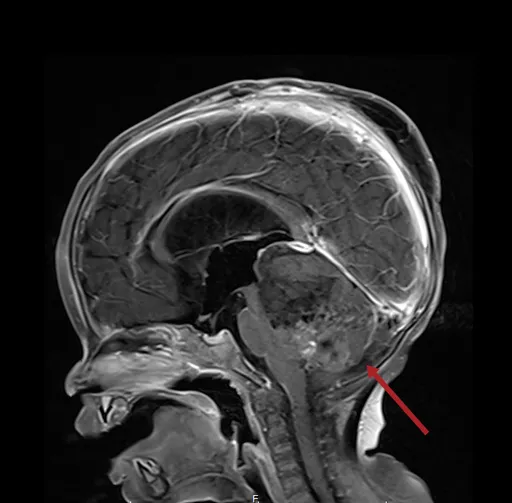

北醫大台北癌症中心兒童腦瘤團隊召集人黃棣棟表示,ATRT是非常罕見的惡性腦瘤,通常好發三歲以下幼童,...